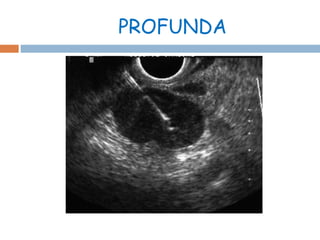

Este documento describe la biopsia aspiración con aguja fina y la citología como métodos de diagnóstico de neoplasias. Explica los pasos para realizar una biopsia aspiración superficial o profunda, el análisis citológico integral de las muestras en diversos aspectos, y las categorías de reporte posibles: benigna, maligina, indeterminada e insuficiente. También menciona algunas técnicas como SurePath, ThinPrep y Pap smear para el análisis de las muestras, y fu